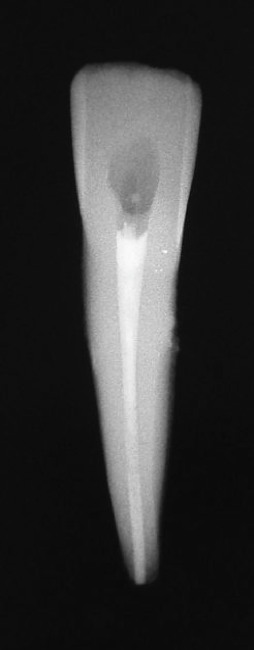

Another time when a post cannot be placed is when there is internal or external resorption. In the case shown in Figure 22, internal resorption occurred. Today it would be much easier to ascertain with CBCT. Here, the clinician filled the resorption with gutta-percha, and then above the gutta-percha, the mid-root coronal section was filled with composite. Because of how weakened the tooth was already, the clinician wanted to do whatever was possible to prevent it from weakening further. Figure 23 shows the postoperative radiograph, and Figure 24 shows the 2-year checkup. The only post that could be placed would have been a fiber post.

Fig 22. Internal resorption.

Figure 22

Fig 23. Postoperative radiograph.

Figure 23

Fig 24. Radiograph at 2-year checkup.

Figure 24